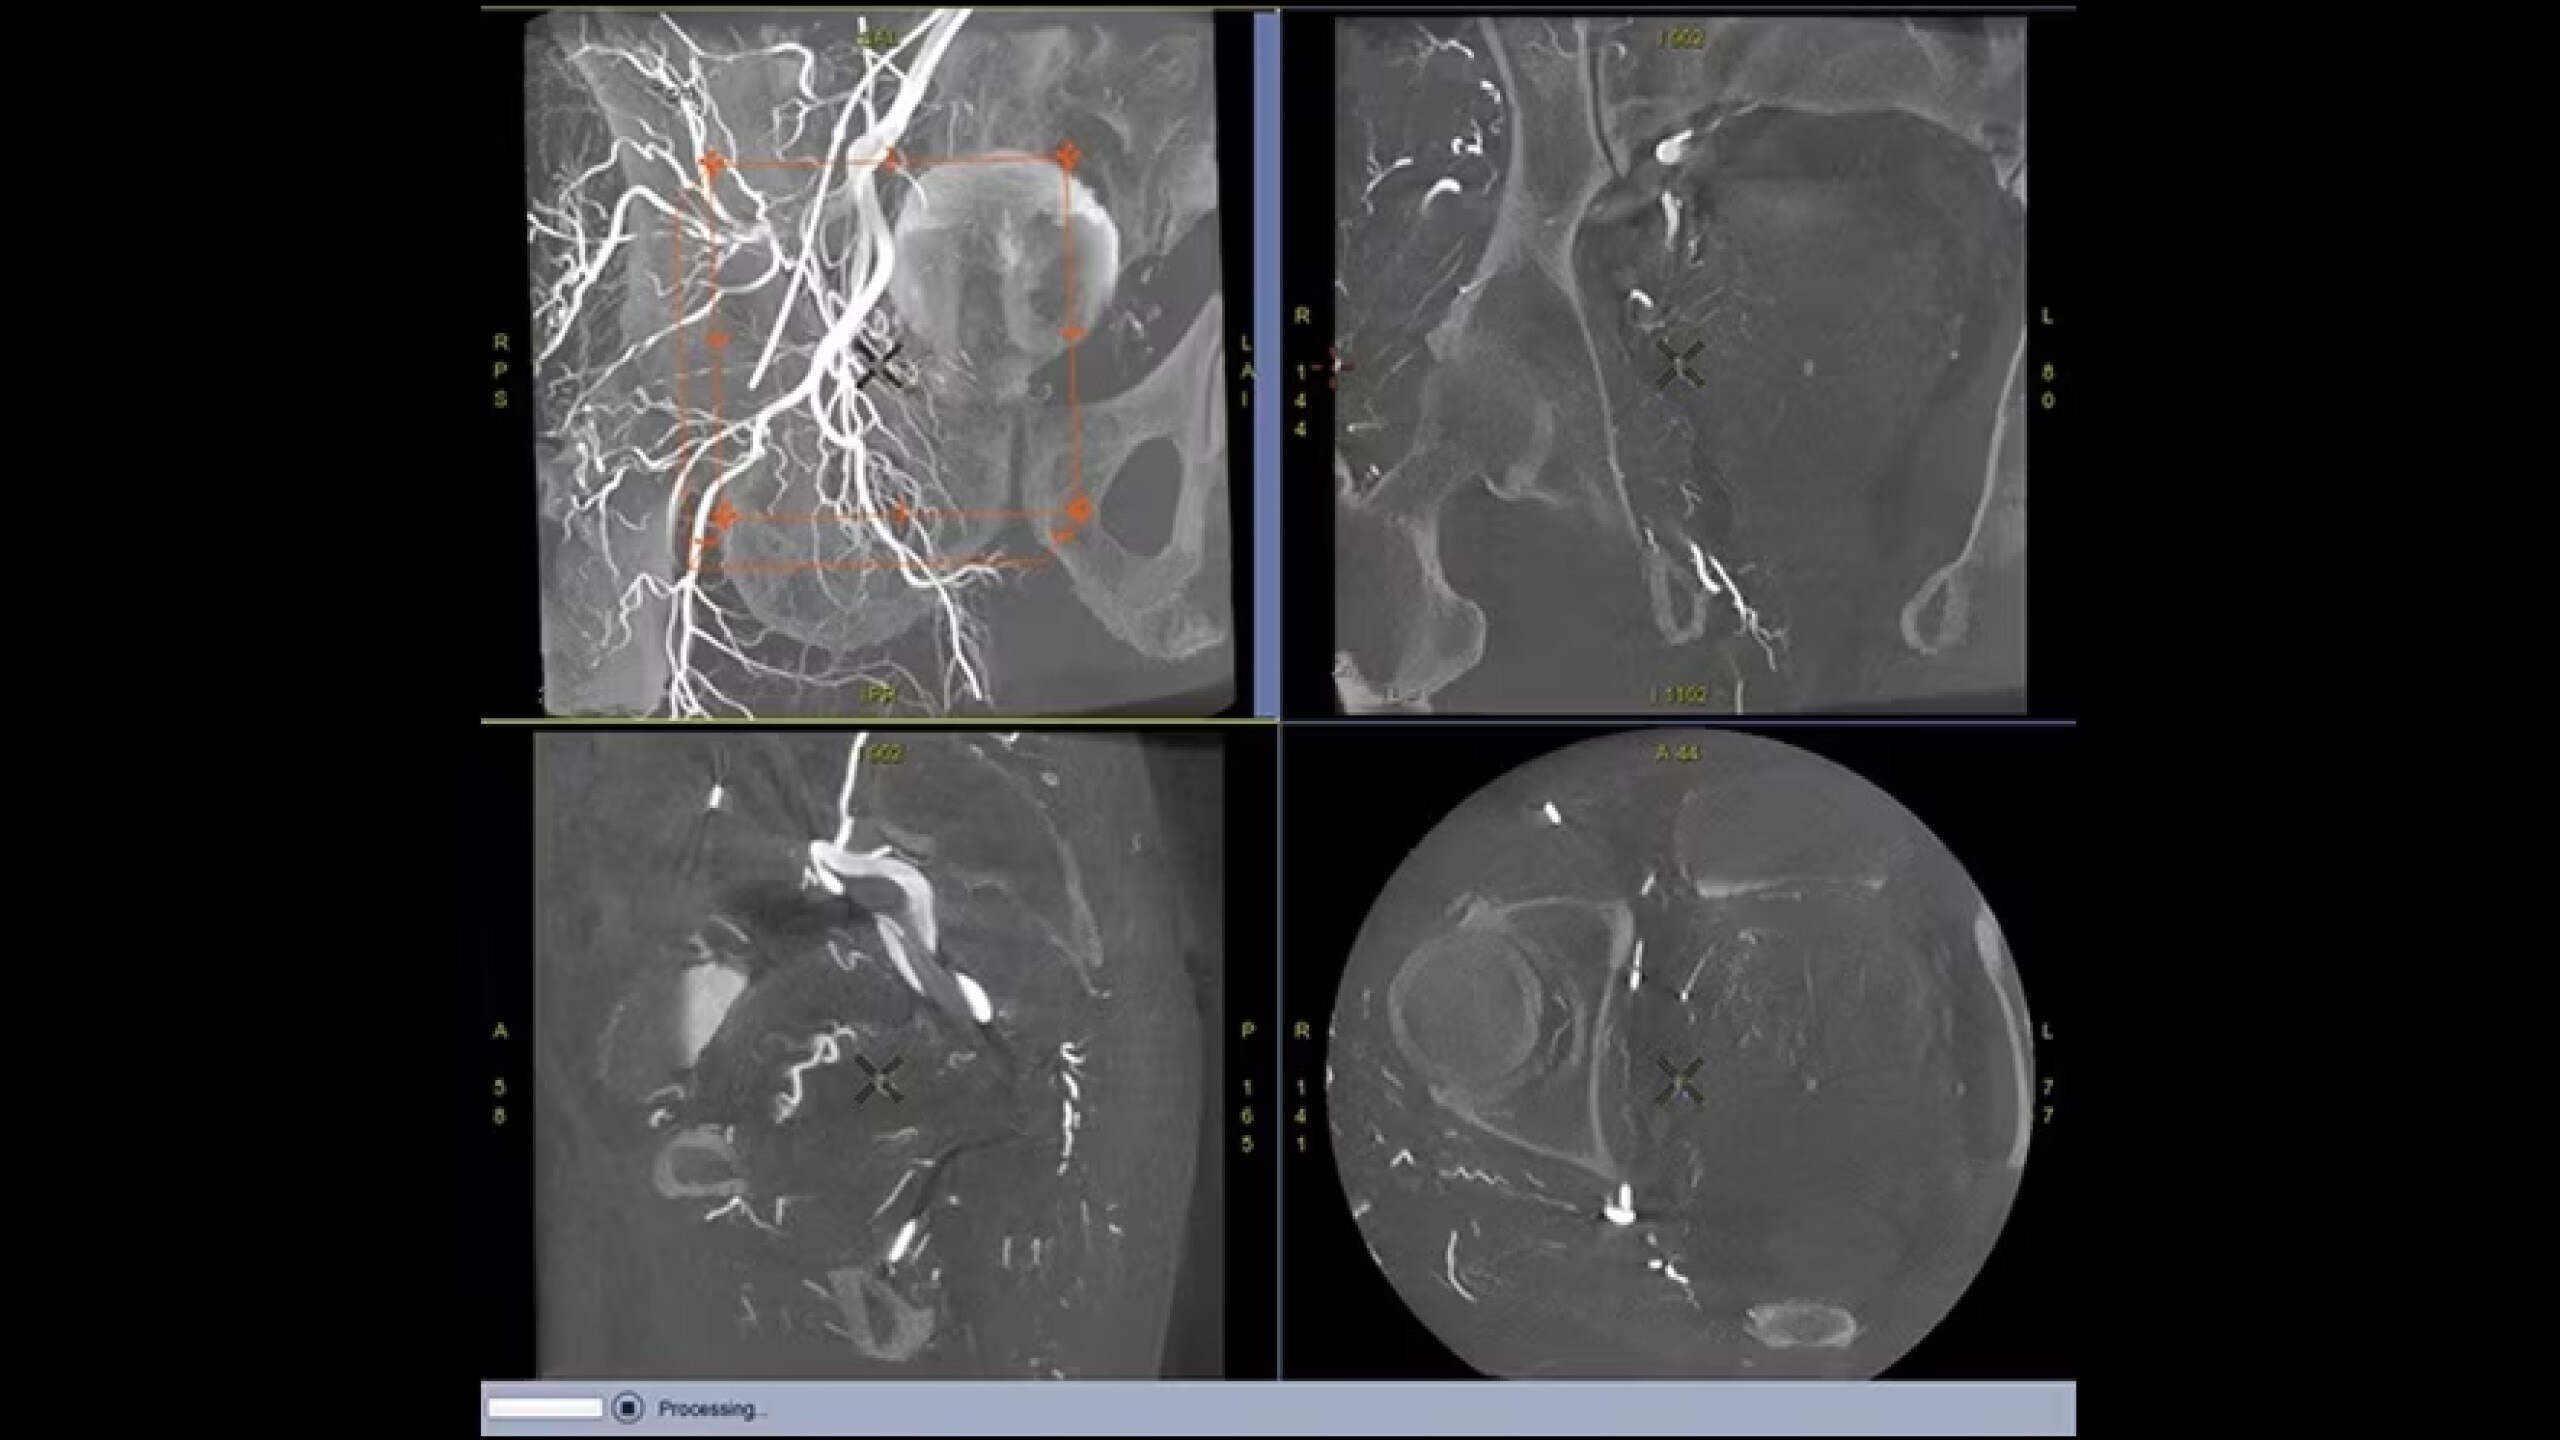

Embo ASSIST is an AI-based augmented guidance solution designed to define optimal embolization strategies and streamline your clinical workflow.

Segment vasculature from CBCT in one click

Visualize multiple vessels and navigate in cross sections to facilitate planning